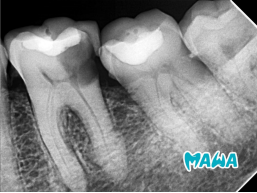

Tratamiento de conducto en dientes con destrucción severa representa uno de los desafíos más comunes en la práctica endodóntica actual. En este caso clínico avanzado, el Dr. Miguel presenta el manejo exitoso de un incisivo central superior derecho (#11) con necrosis pulpar y importante pérdida de estructura coronaria.

- Diente: #11 – Incisivo central superior derecho

- Diagnóstico pulpar: Necrosis Pulpar

- Desafío principal: Destrucción coronaria severa que requería reconstrucción pre-endodóntica para lograr un aislamiento absoluto efectivo.

La destrucción severa de la corona comprometía seriamente la posibilidad de obtener un campo operatorio limpio y libre de contaminación. Por esta razón, la reconstrucción previa se convirtió en el pilar fundamental de todo el tratamiento.

La primera fase consistió en la reconstrucción de la corona del diente #11. Este paso fue esencial para transformar un diente con estructura extremadamente comprometida en un diente con aislamiento predecible. Una vez reconstruida la anatomía coronaria, se procedió al aislamiento absoluto con dique de goma, asegurando un campo operatorio completamente estéril.